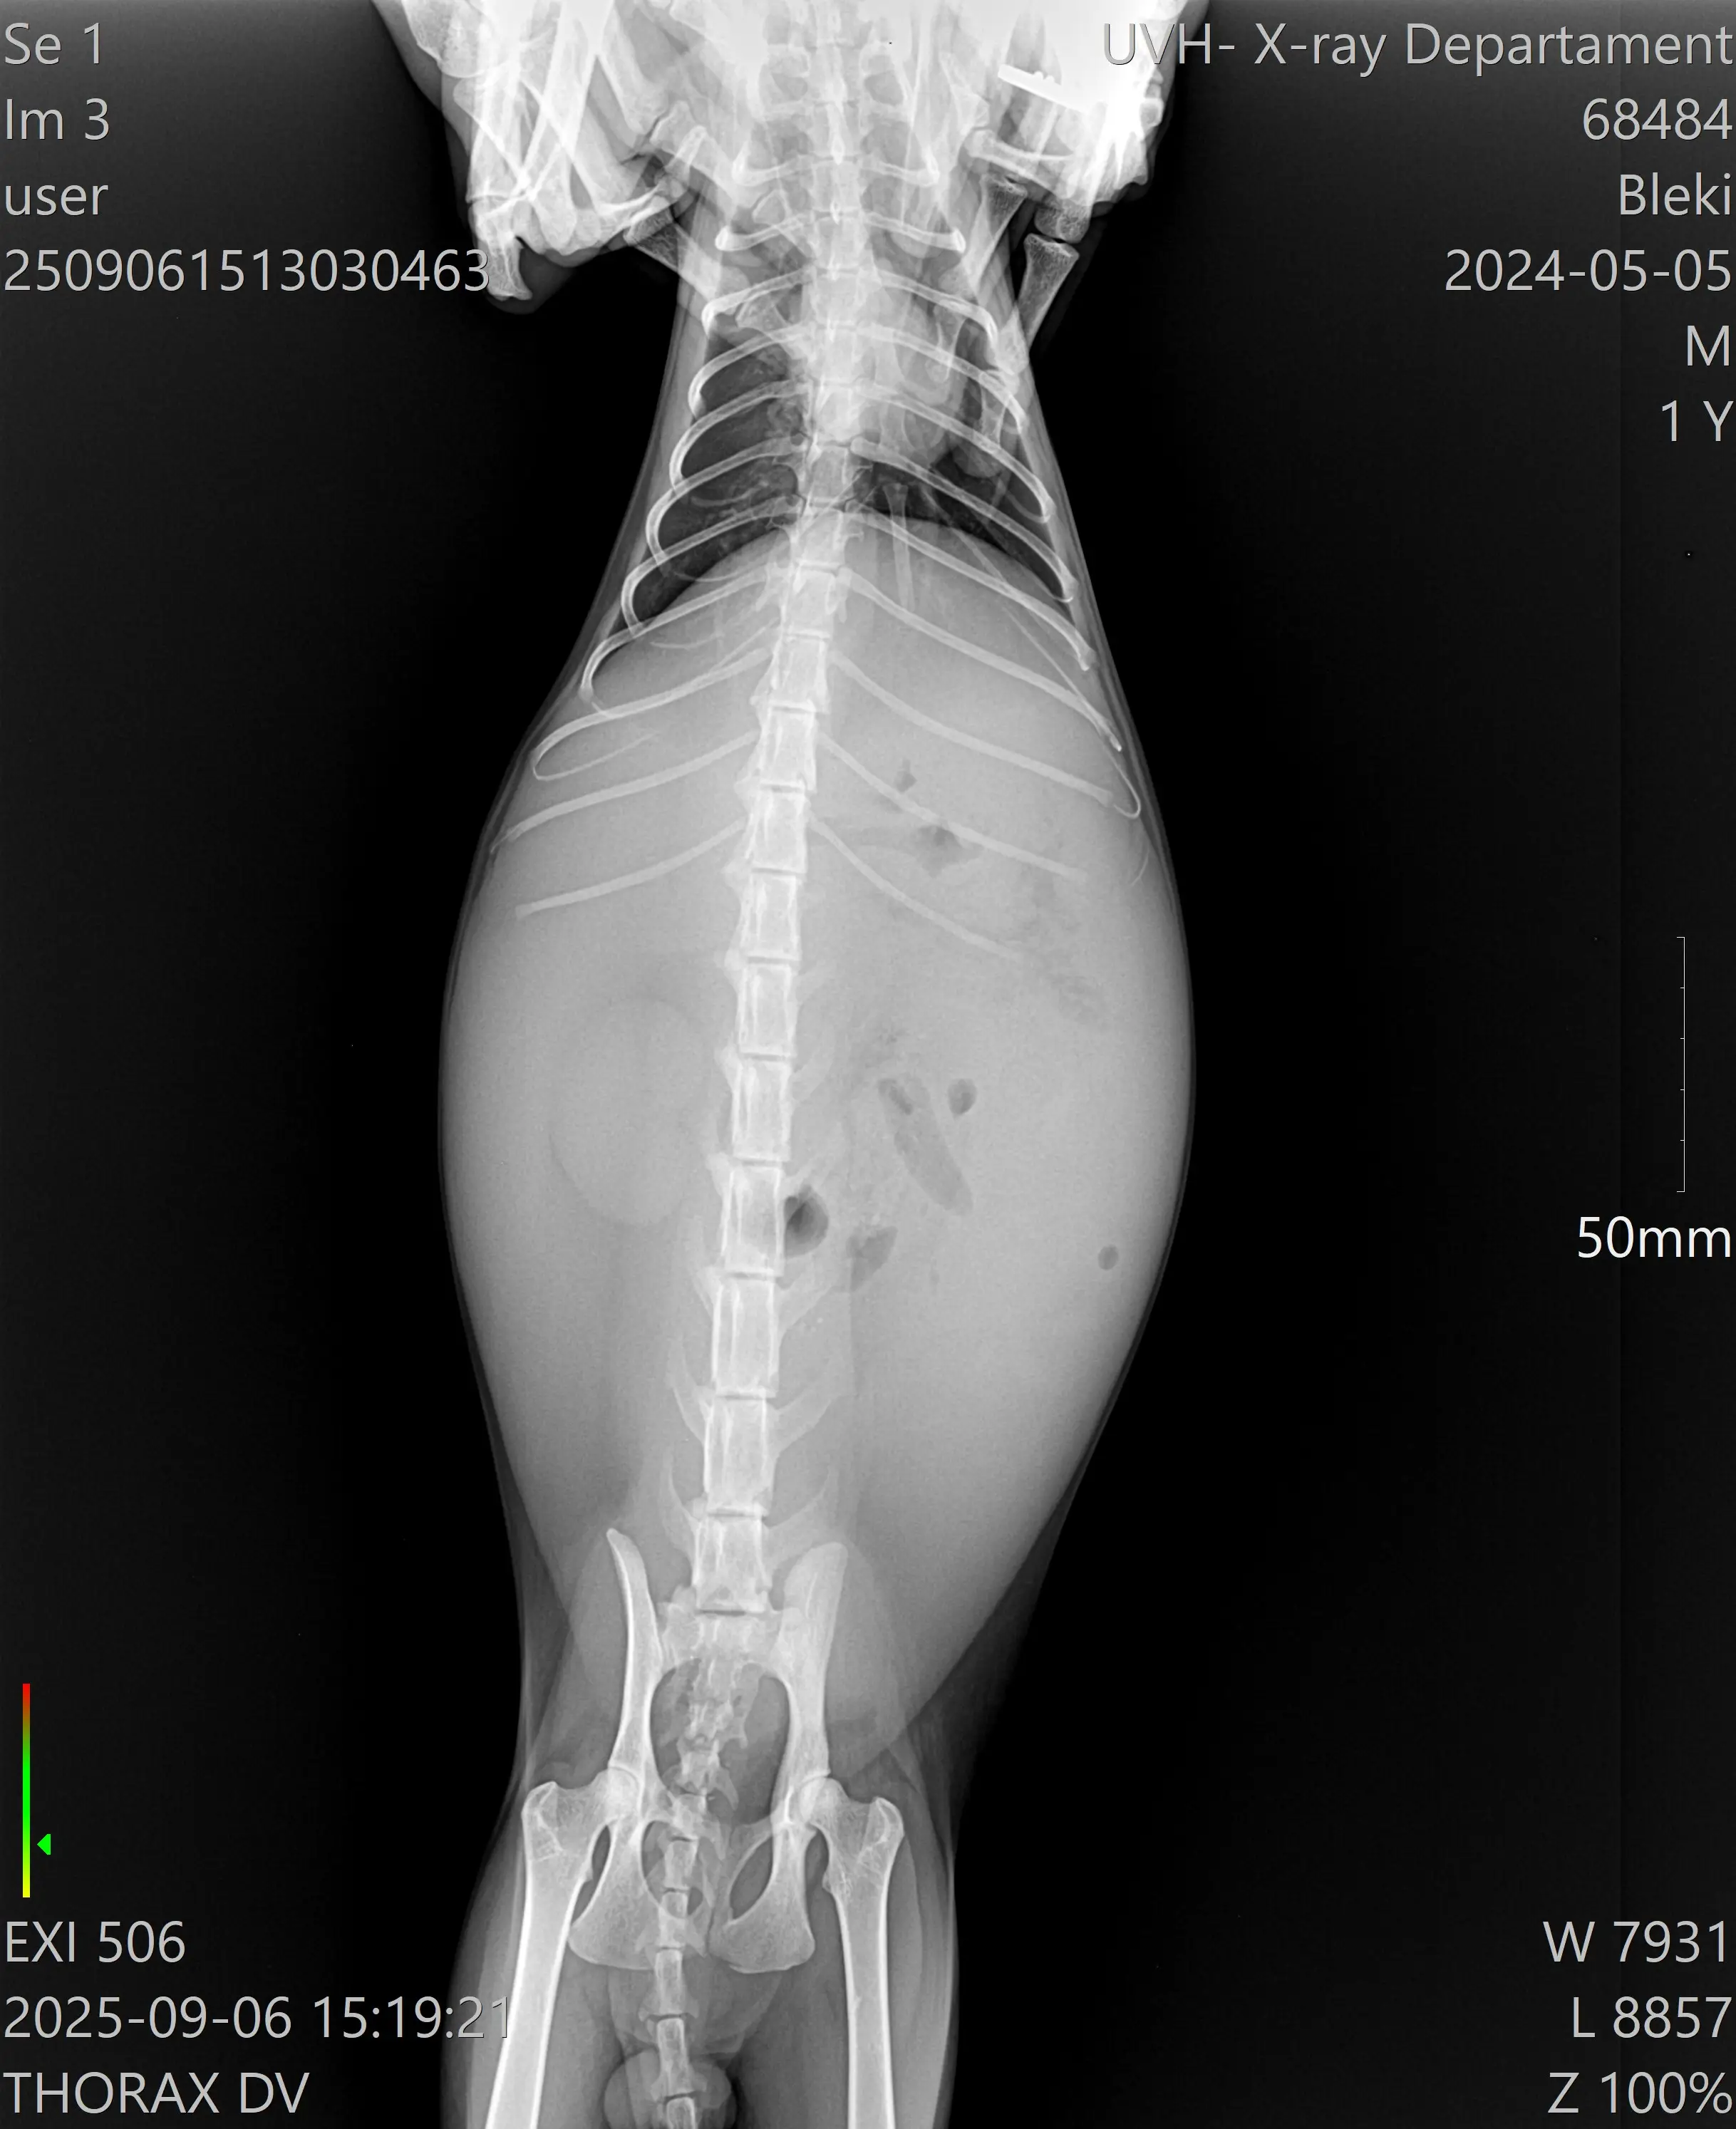

Преди година и половина съдбата ме срещна с едно безпомощно новородено коте – малко, болно, едва дишащо, с тежко увредени очички и без никакъв шанс да оцелее самичко. Борихме се заедно – хранех го със спринцовка, капех очите му, държах го в шепи нощем… И той оцеля! Не просто оцеля, а се превърна в най-прекрасния, буен и силен котарак – с лъскава козина, огромно тяло и още по-голям характер. Блеки е душата на дома ми – моето момче, без което нищо няма да е същото.Преди две седмици обаче чухме най-страшната диагноза – инфекциозен перитонит (FIP), мокра форма. Коремчето му е подуто, не се храни, отслабва и само лежи… Лекарите ни изписаха медикаменти, но честно казано казаха, че шансовете са минимални,но ние не се отказах отказахме продължихме да търсим варианти ,да питаме навсякъде и за съжаление, докато намерим правилната посока на лечение състоянието му доста се влоши .

И все пак – надежда има! Един човек от София с голямо „Ч“ ни подаде ръка и ни помогна с първите три ампули от животоспасяващото лекарство GS, с което Блеки може да има шанс. И вече ефект след седмица поставяне има ,храни се започна да изглежда жив. Но лечението за мен е непосилно като бъдеща студентка – нужно е ежедневно прилагане на медикамента в продължение на 87 дни.